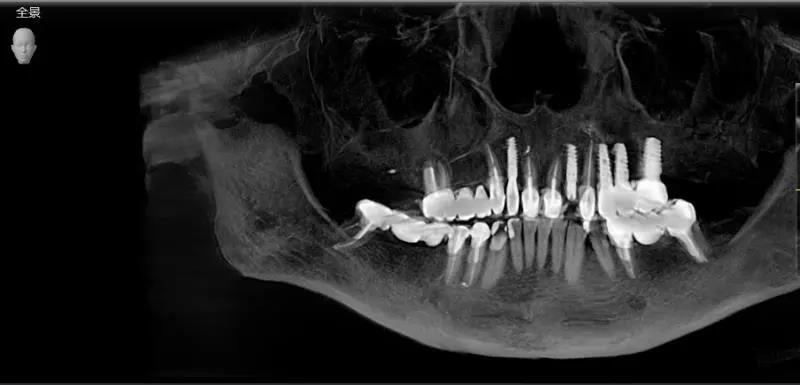

海德堡联合口腔重新定义德国种植牙标准,在UNIC全息数字化种植中心将复杂的种植流程串连形成数字化闭环,提高种植品质,将误差减少到更小,维护术后种植体稳定性较强、成活率较高。